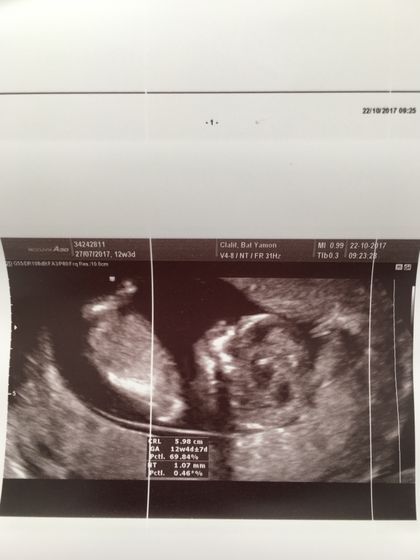

Вот и мы сегодня прошли наш первый скрининг) волновалась жуть… по УЗИ вроде всё хорошо ? врач был не русскоязычный, поэтому я толком ничего не спрашивала) единственное он уверенно сказал, что у нас мальчик и всё хорошо!!!) ктр 6см. срок 12.4 на один денёк опережаем месячные)) Риски по возврату-1:1249, а по результатам УЗИ 1:8327. Результаты анализа крови, будут аж через 2 недели. Кто делал скрининг на моем сроке? Какие у вас результаты?

У меня тоже срок был 12,4 недели. Тоже 6 см. Базовый риск трисомии 21 для 31 года 1:564, индивидуальный 1:11240 — это уже по крови, по УЗИ вроде не рассчитывали такой риск, нет такой записи.